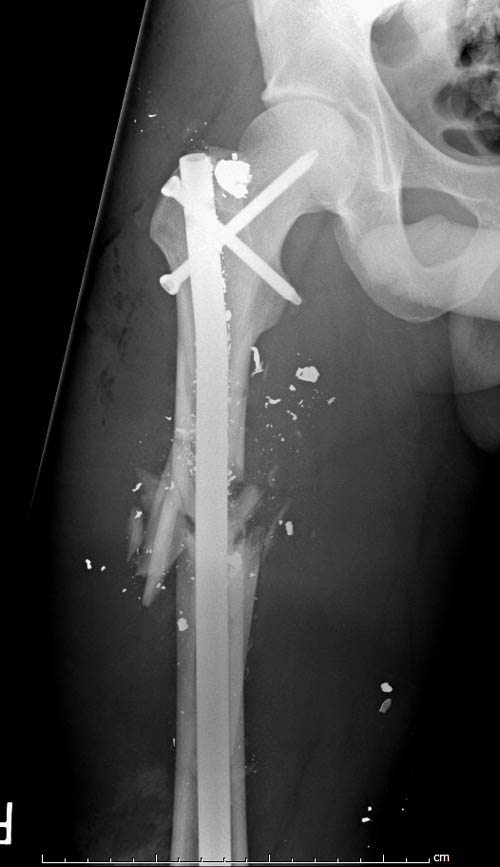

На снимках осложнение огнестрельного перелома бедра поздней инфекцией. 7

лет назад оперирован: правое бедро, сперва на ExFix, затем заменен на

гвоздь, а левая - гвоздь при поступлении.